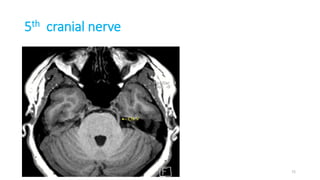

5th cranial nerve